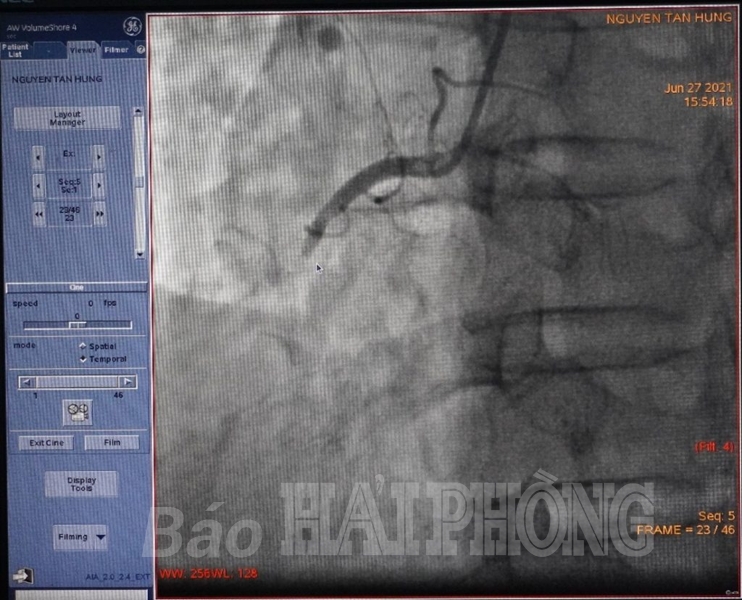

Bằng những biện pháp xử lý nhanh chóng, người bệnh được chỉ định dùng thuốc để nâng huyết áp và can thiệp động mạch vành cấp cứu. Khi chụp động mạch vành, các bác sĩ nhận thấy động mạch vành phải tắc hoàn toàn. Đây là động mạch vô cùng quan trọng, đóng vai trò cung cấp máu cho một vùng cơ tim khá lớn. Ngay lập tức, người bệnh được thông mạch tắc và đặt một stent để tái lưu thông mạch máu. Sau can thiệp, người bệnh ổn định và được tiếp tục chuyển lên điều trị tại phòng cách ly riêng biệt thuộc Khoa Tim mạch. Hiện tại, người bệnh tỉnh táo, không còn đau tức ngực, huyết áp và nhịp tim đã ổn định./.